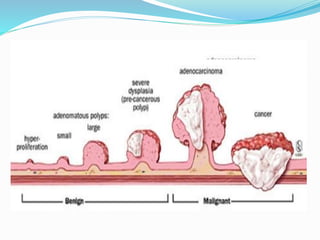

This document discusses colorectal polyps. It defines polyps and describes their types, including neoplastic and non-neoplastic polyps. It discusses adenomatous polyps in depth, noting their malignant potential increases with size over 1cm and villous architecture. Radiological diagnostic methods for polyps including single and double contrast barium enema and CT colonography are explained. The document provides an overview of polyp pathogenesis and genetic syndromes like FAP that increase cancer risk.